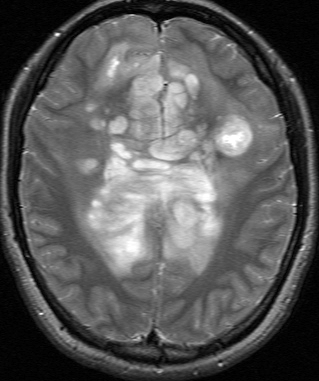

これは30歳くらいの若い女性にできた乏突起膠腫です。軽いけいれん発作を生じましたがその後は無症状です。上がT2強調画像で,下がガドリニウム増強像です。CTでは石灰化が散在していました。大脳深部をほとんど埋めるように腫瘍は浸潤して広がっています。脳外科の先生にこの患者さんが無症状だといっても信じてもらえないのですが本当です。

ほんの少しだけ腫瘍をとって(生検術)病理診断を確定しました。

腫瘍が大きすぎるので,認知機能を保つために,全脳照射30グレイとテモゾロマイド化学療法を2年しました。以来9年以上たちますが,とても頭の良い方でちゃんと働いておられます。

この患者さんから学ぶことはたくさんあります。この広範に伸展した腫瘍はおそらく10歳前後から存在したのだと想像されます。腫瘍が発見されず未治療だったからこそ,これまで通常の生活ができたのかもしれません。

また,グレード2の乏突起膠腫には限りなくグレード1に近い高分化型の腫瘍が存在するということです。乏突起膠腫は手術で完全摘出できれば治るのでしょうが,手術によって認知機能障害や高次脳機能障害を生じれば社会生活を一人ですることは難しくなります。分化型の乏突起膠腫は,正常の神経細胞や脳機能を破壊しないで浸潤増大しますから,脳の中にこんなに広がっても,何の症状も出さないということがあります。同じグリオーマでも膠芽腫などと比べれば大きな差があるのです。治療後の生存の質を考える時に,このような例があるということを思い出すことは大切です。